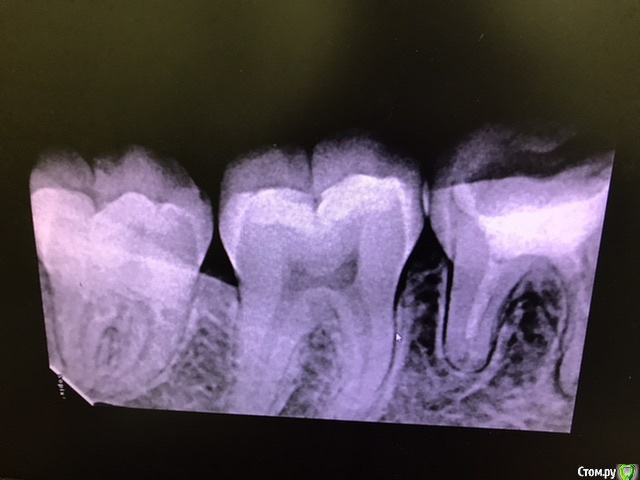

В середине марта обратилась на перелечивание каналов с гранулемой в 46 зубе.

Прикрепляю рентген до, 3 рентгена после первого лечения, рентген после установки гуттаперчевых штифтов. Также есть КТ до перелечивания, вдруг кто-то заинтересуется.